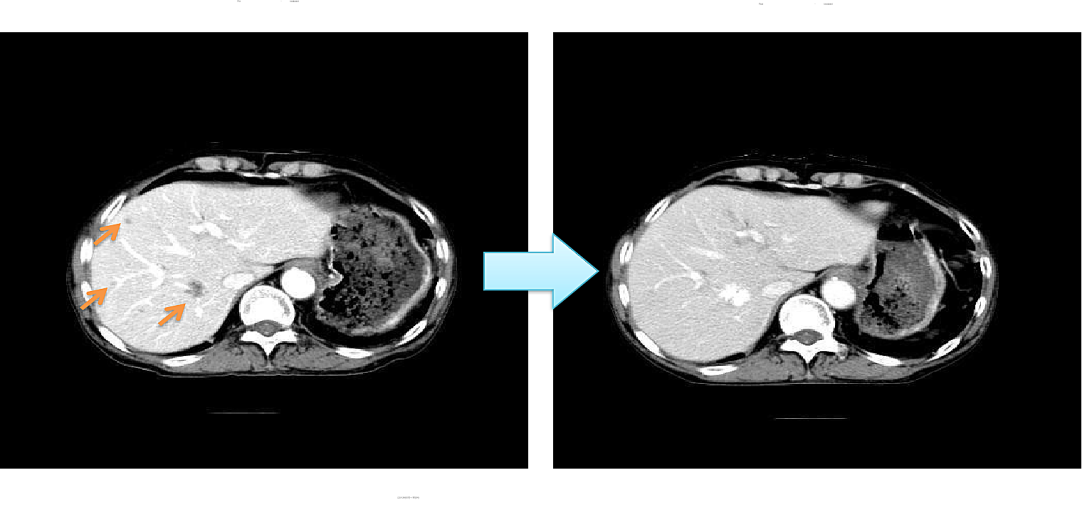

非小细胞肺癌肝转移经rAd-p53+rAd-p53-DC+LAK联合治疗效果

(1疗程: 3次免疫细胞注射)

影像结果显示,经过今又生联合免疫细胞治疗后,肝脏3个转移灶完全消失,疗效显著。